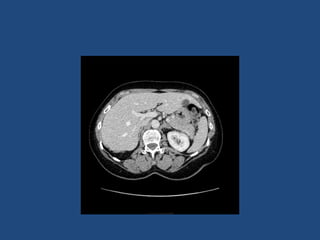

Imaging

• CT better at eliminating malignancy

(dedicated CT looking at Hounsfield units (HU)

and washout characteristics)

– <10HU = benign (sens 71%, spec 100%)

• MRI may characterise phaeos better

• FDG-PET good for phaeos and cancer

• FNA – consider if cancer history and >10HU on CT

after exclusion of phaeo

Imaging - size

• >4cm 90% sensitivity carcinomas

24% specificity (ie only 24% cancer)

• >6cm 25% chance of it being carcinoma

• <2cm + hypodense then unlikely to grow

• If change in size >1cm over 6 months consider

resection